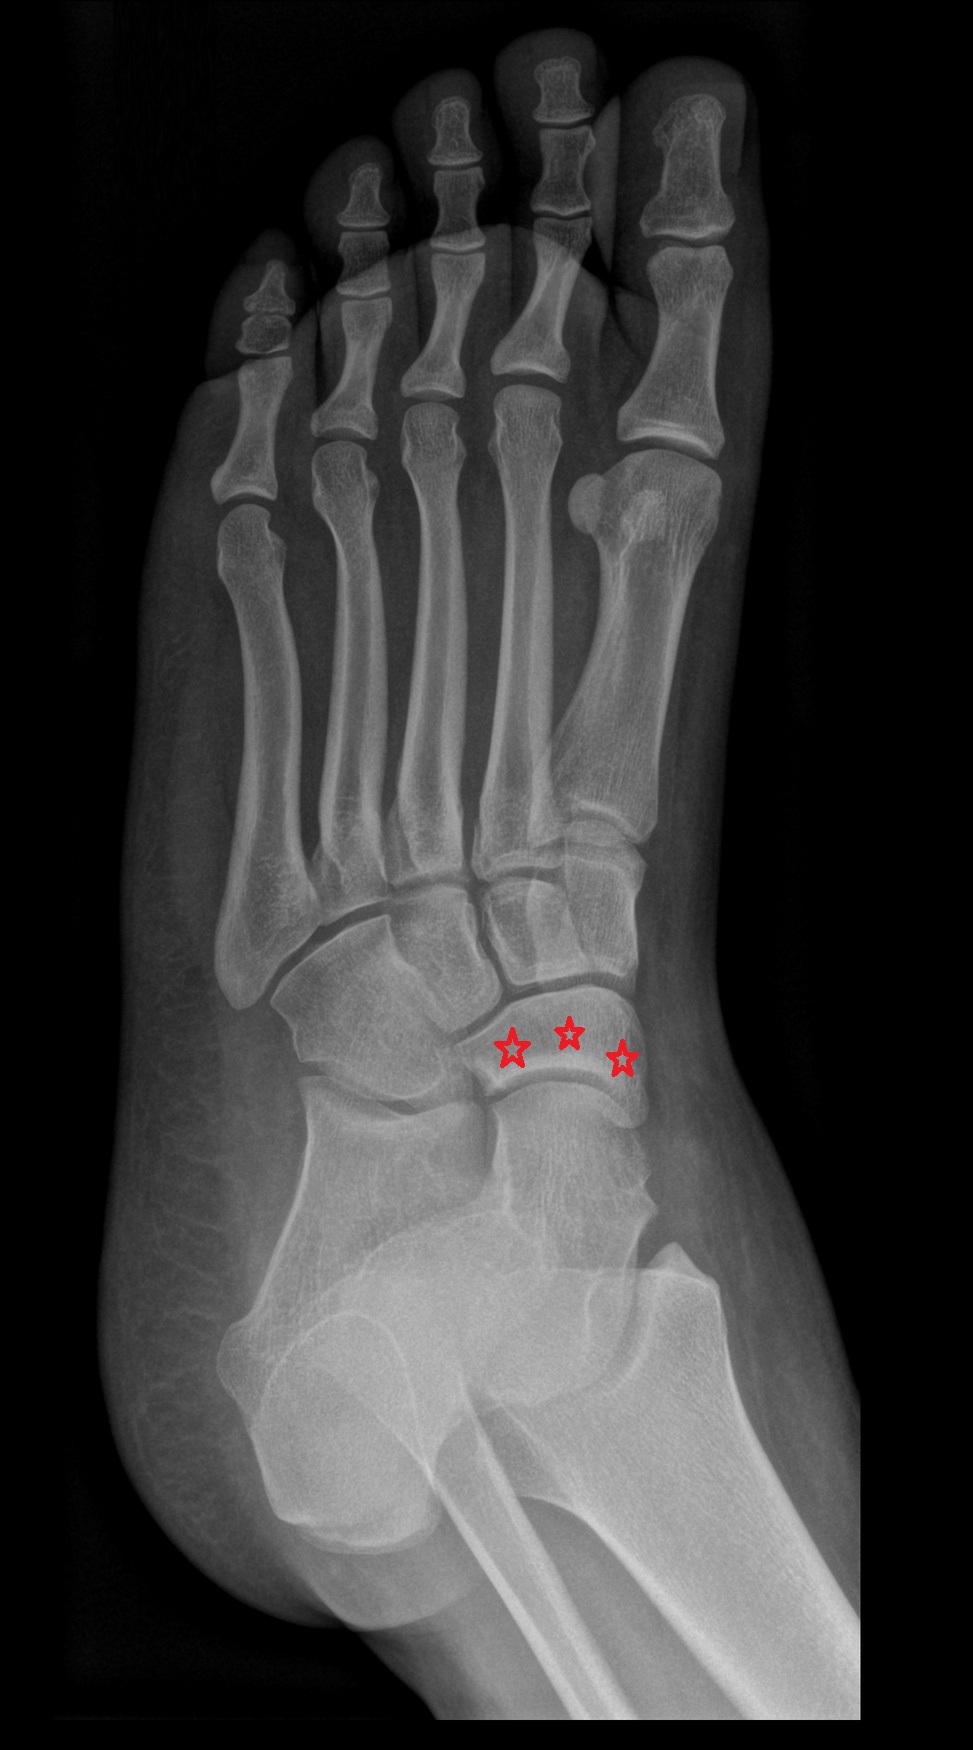

- Talus

- Head of talus

- Neck of talus

- Calcaneus

- Cuboid

- Medial malleolus

- Lateral malleolus

- Lateral cuneiform bone

- Medial cuneiform bone

- Intermediate cuneiform bone

- Navicular bone

- First metatarsal bone

- Second metatarsal bone

- Third metatarsal bone

- Fourth metatarsal bone

- Fifth metatarsal bone